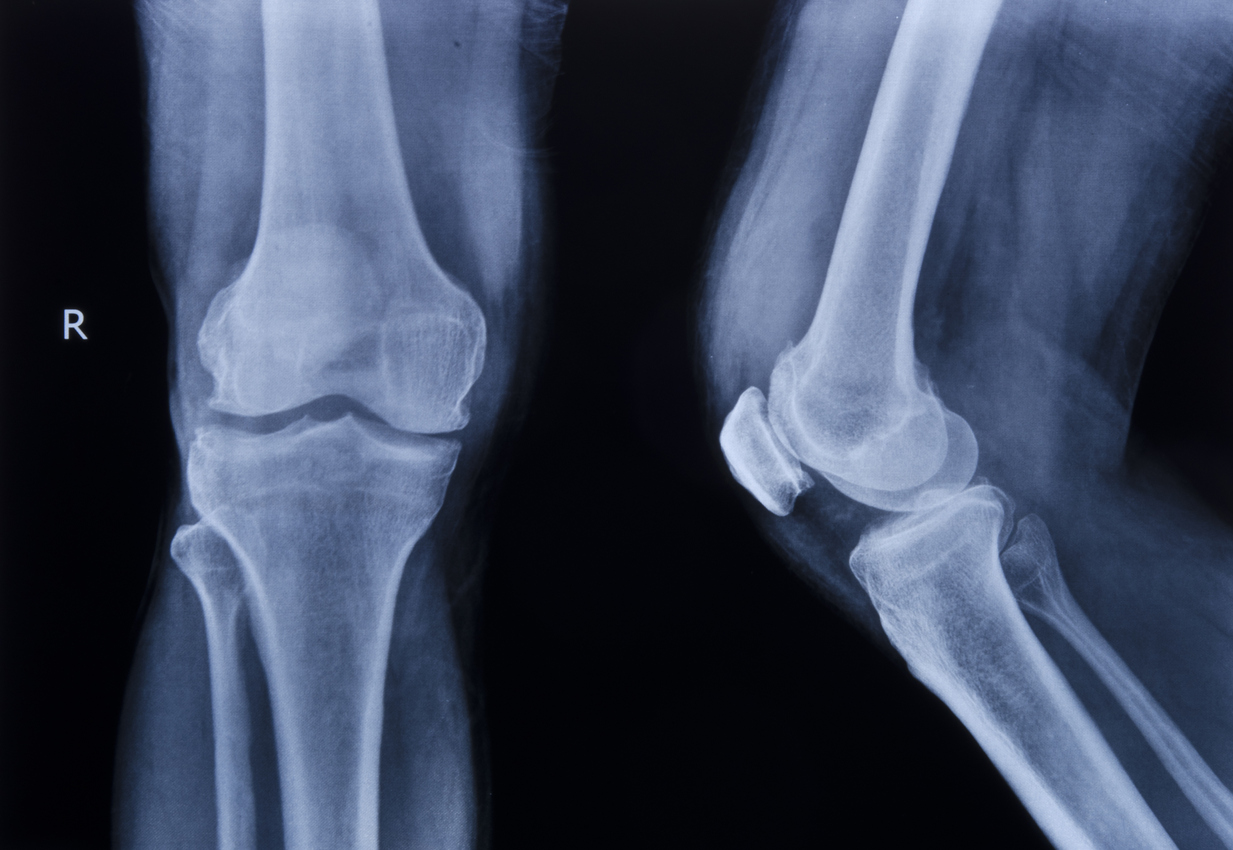

Common Slip and Fall Knee Injuries

Knee injuries from a slip and fall run the gamut from soft tissue injuries like strains to fractures and other serious injuries:

• Fractures. The kneecap or patella is most likely to fracture in a fall.

• Torn tendons. The quadriceps and patellar tendons are most likely to be torn in a fall, making it hard to straighten your leg.

• Torn ligaments. Any of the four major knee ligaments may be torn in a fall and destabilize the knee joint.

• Meniscus tears involving the C-shaped cartilage cushioning the joint. Tears may need only rest and physical therapy, but severe tears may require surgery.

• Knee dislocation. This happens when the kneecap is forced from its normal position in a groove in the bone.

Any of these injuries may require extended rehabilitation and surgery, potentially with long-term impairment. Possible consequences include long-term joint instability, early-onset arthritis in the knee, and the need for joint replacement.